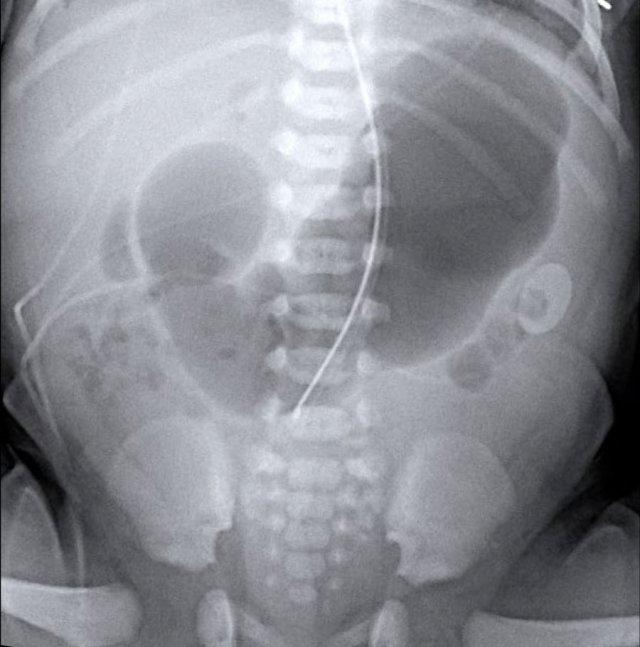

Các dấu hiệu bao gồm:

- Nhiều quai ruột non giãn

- Khí trong thành ruột (Pneumatosis intestinalis).

- Tràn khí ổ bụng (Pneumoperitoneum).

Chẩn đoán:

Viêm ruột hoại tử (NEC) có thủng ruột.